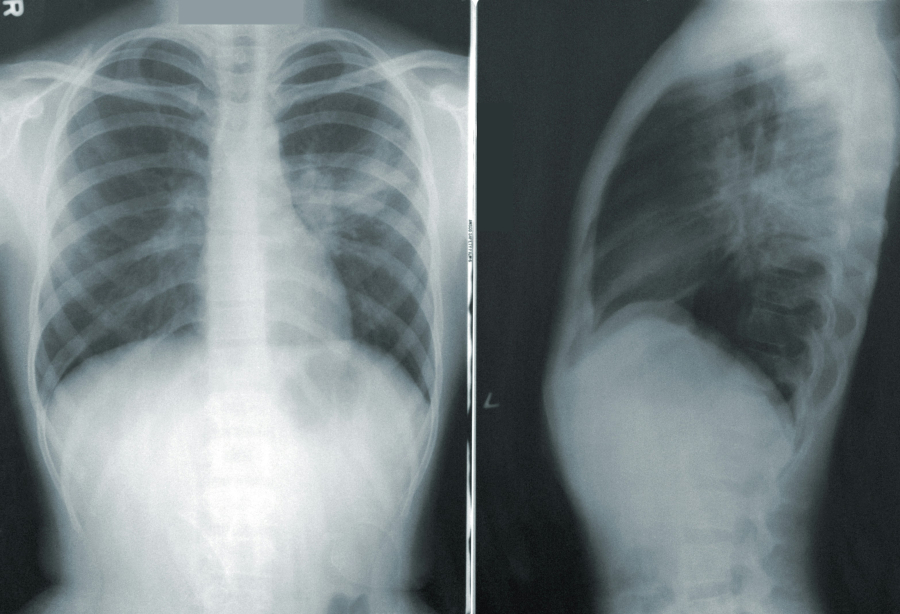

Τα συμπτώματα του καρκίνου του πνεύμονα διαφέρουν μεταξύ των ασθενών. «Όταν ο καρκίνος αυτός δίνει συμπτώματα, αυτά μπορεί να προέρχονται από την επίδραση που έχει σε μέρη του θώρακα, γεγονός που μπορεί να οδηγήσει σε πόνο στο στήθος, βήχα με αίμα ή δύσπνοια», δηλώνει ο Boffa.

Αν και ο βήχας δεν είναι αποκλειστικά ένδειξη για καρκίνο του πνεύμονα, ένας βήχας που επιμένει για εβδομάδες (ειδικά χωρίς άλλη συνοδό νόσο) θα πρέπει να προκαλέσει μια κάποια ανησυχία.

Ο επίμονος βήχας συνήθως σχετίζεται με πιο προχωρημένο καρκίνο του πνεύμονα, όπως το στάδιο 3 ή 4 - δηλώνει ο Yang.

Ένας παρατεταμένος βήχας μπορεί επίσης να είναι σύμπτωμα πνευμονίας, ενώ μεταξύ 50-70% των ατόμων με καρκίνο του πνεύμονα αναπτύσσουν πνευμονία (πνευμονική λοίμωξη) λόγω εξασθενημένου ανοσοποιητικού συστήματος.